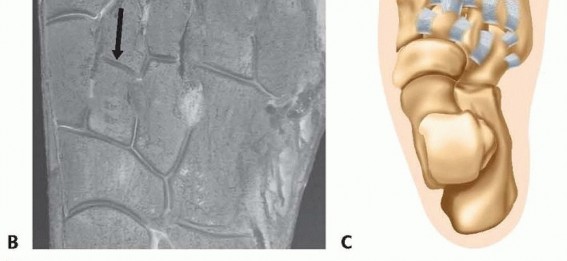

FIG 1

A.

Axial CT image depicting the Roman arch configuration of the tarsometatarsal joints.

B.

Anatomic specimen demonstrating the keystone of the Roman arch: The second metatarsal base is recessed between the medial and lateral cuneiforms (

black arrow

).

C.

Ligamentous connections of the tarsometatarsal region.